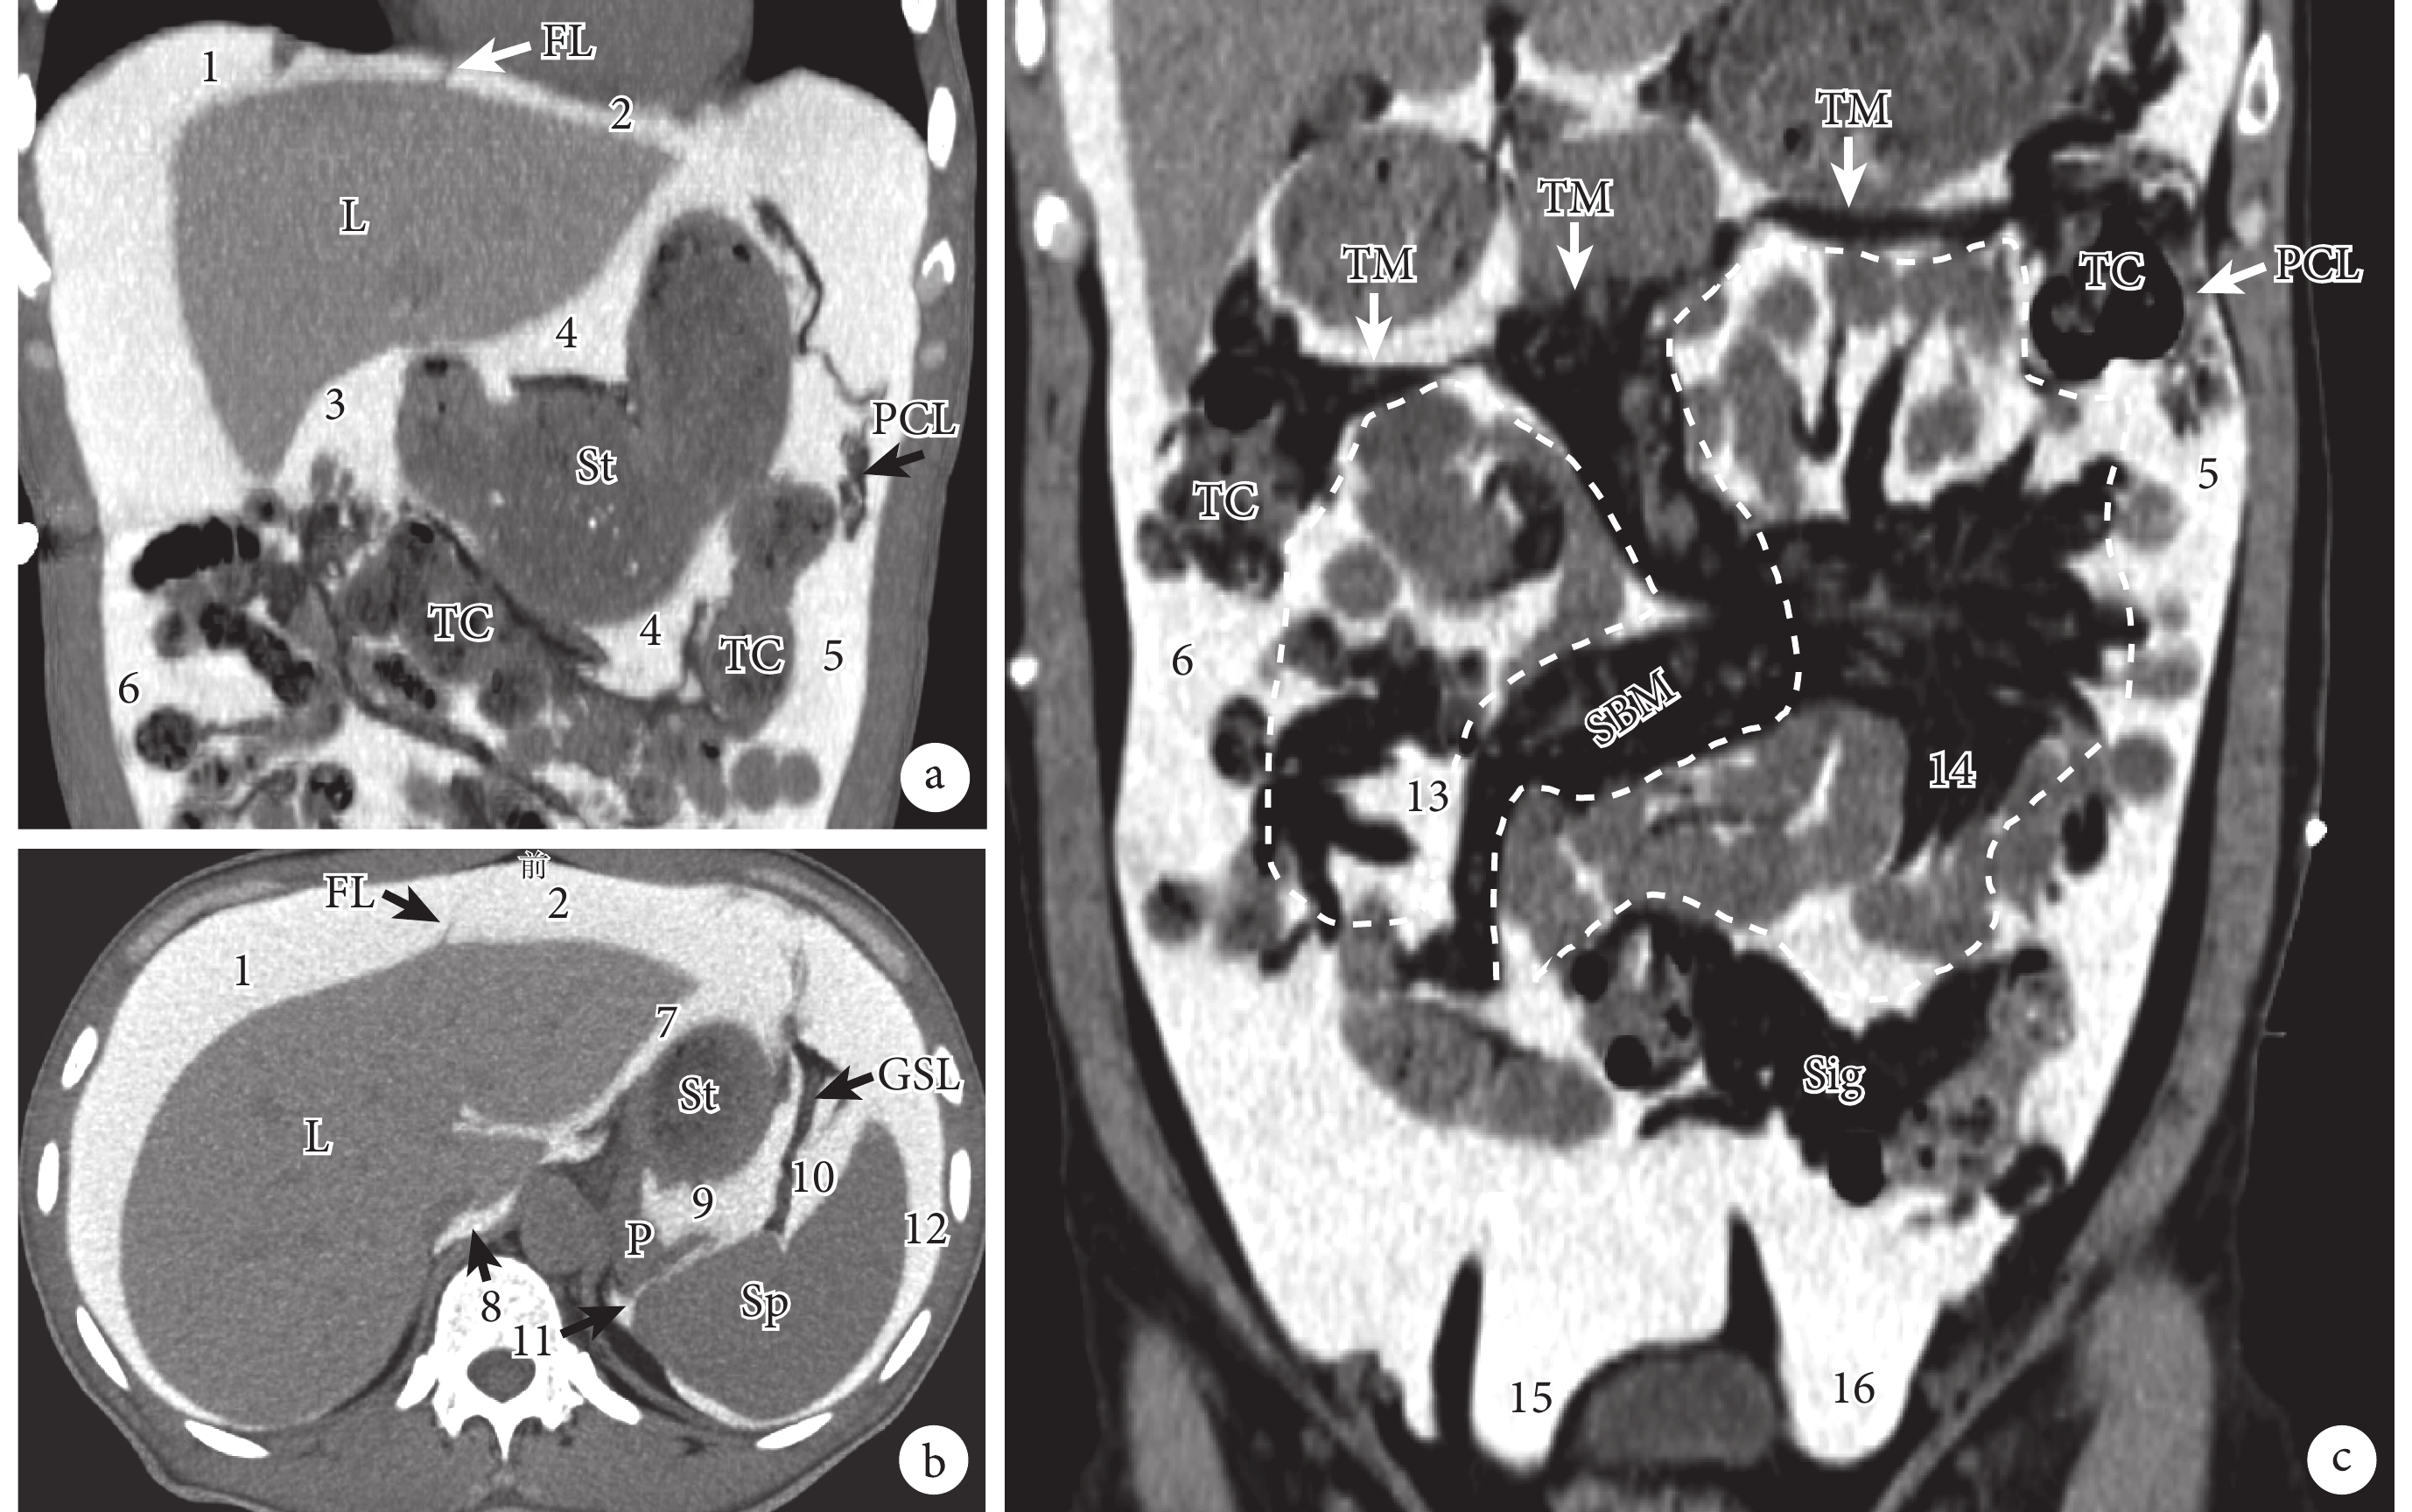

a、b:結腸上區的主要腹膜腔間隙;c:結腸下區的主要腹膜腔間隙。1:右肝上間隙;2:左肝上間隙;3:右肝下間隙;4:網膜囊;5:左結腸旁溝;6:右結腸旁溝;7:左肝下間隙;8:網膜囊上隱窩;9:網膜囊脾隱窩;10:胃脾隱窩;11:脾腎隱窩;12:脾外側間隙(脾周圍隱窩);13:右結腸下間隙;14:左結腸下間隙;15:右直腸旁窩;16:左直腸旁窩;FL:鐮狀韌帶;L:肝臟;St:胃;PCL:膈結腸韌帶;TC:橫結腸;GSL:胃脾韌帶;P:胰腺;Sp:脾臟;TM:橫結腸系膜;SBM:小腸系膜;Sig:乙狀結腸

結腸上區位于橫膈和橫結腸及橫結腸系膜之間,以肝鐮狀韌帶為界又被分為右結腸上區和左結腸上區(圖2a、2b)。結腸上區的解剖較為復雜,并且對于結腸上區各腹膜腔間隙的命名也并未達成完全一致[2-3, 5-6]。

結腸下區位于橫結腸及橫結腸系膜下方,其以小腸系膜根部、降結腸和升結腸為界分為左、右結腸旁溝及左、右結腸下間隙(圖2c)。左、右結腸旁溝(paracolic gutter)分別是位于降結腸和升結腸旁邊的后腹壁上的腹膜凹陷(隱窩),并且大部分位于結腸的外側。左結腸旁溝向上受到膈結腸韌帶部分阻擋,向下與盆腔相通;右結腸旁溝向上通向右肝下間隙、右肝上間隙,向下與盆腔相通。左、右結腸下間隙(infracolic space),國內解剖學界稱之為腸系膜竇。右結腸下間隙位于小腸系膜根部與升結腸之間,由盲腸、升結腸、闌尾系膜和左側的小腸系膜限定;左結腸下間隙位于小腸系膜根部與降結腸之間,其下方開口與盆腔相通。